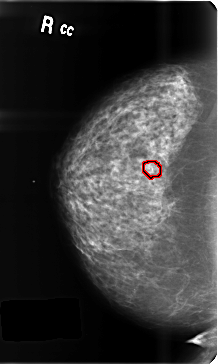

B_3459_1.RIGHT_CC

RIGHT_CC LINES 4728 PIXELS_PER_LINE 2832 BITS_PER_PIXEL 12 RESOLUTION 50 OVERLAY

FILE: B_3459_1.RIGHT_CC.OVERLAY

TOTAL_ABNORMALITIES 1

ABNORMALITY 1

LESION_TYPE CALCIFICATION TYPE PLEOMORPHIC DISTRIBUTION CLUSTERED

ASSESSMENT 4

SUBTLETY 4

PATHOLOGY BENIGN

TOTAL_OUTLINES 1

BOUNDARY